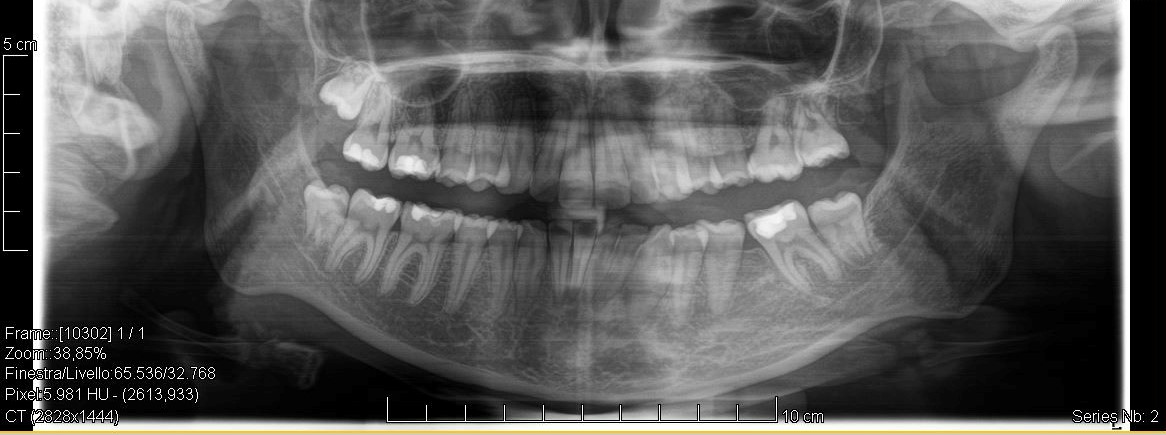

Ortopanoramica pre-trattamento della paziente. I due primi molari sinistri appaiono irrimediabilmente compromessi da carie destruenti

Fig. 1 Ortopanoramica pre-trattamento della paziente. I due primi molari sinistri appaiono irrimediabilmente compromessi da carie destruenti